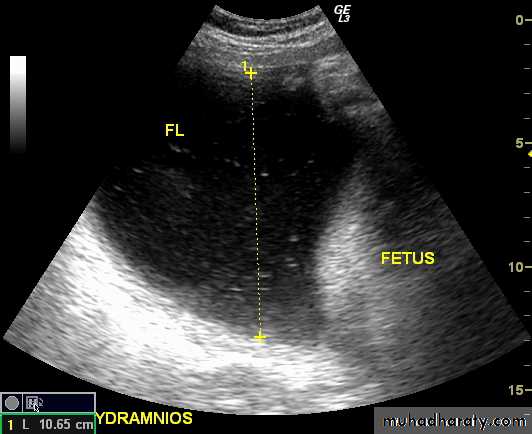

Poly hydraminos refers to a situation where the amniotic fluid volume is more than expected for gestational age.It is generally defined as:

amniotic fluid index (AFI) > 25 cmlargest fluid pocket depth (maximal vertical pocket (MVP)) greater than 8 cm

overall amniotic fluid volume larger than 1500-2000 cc3